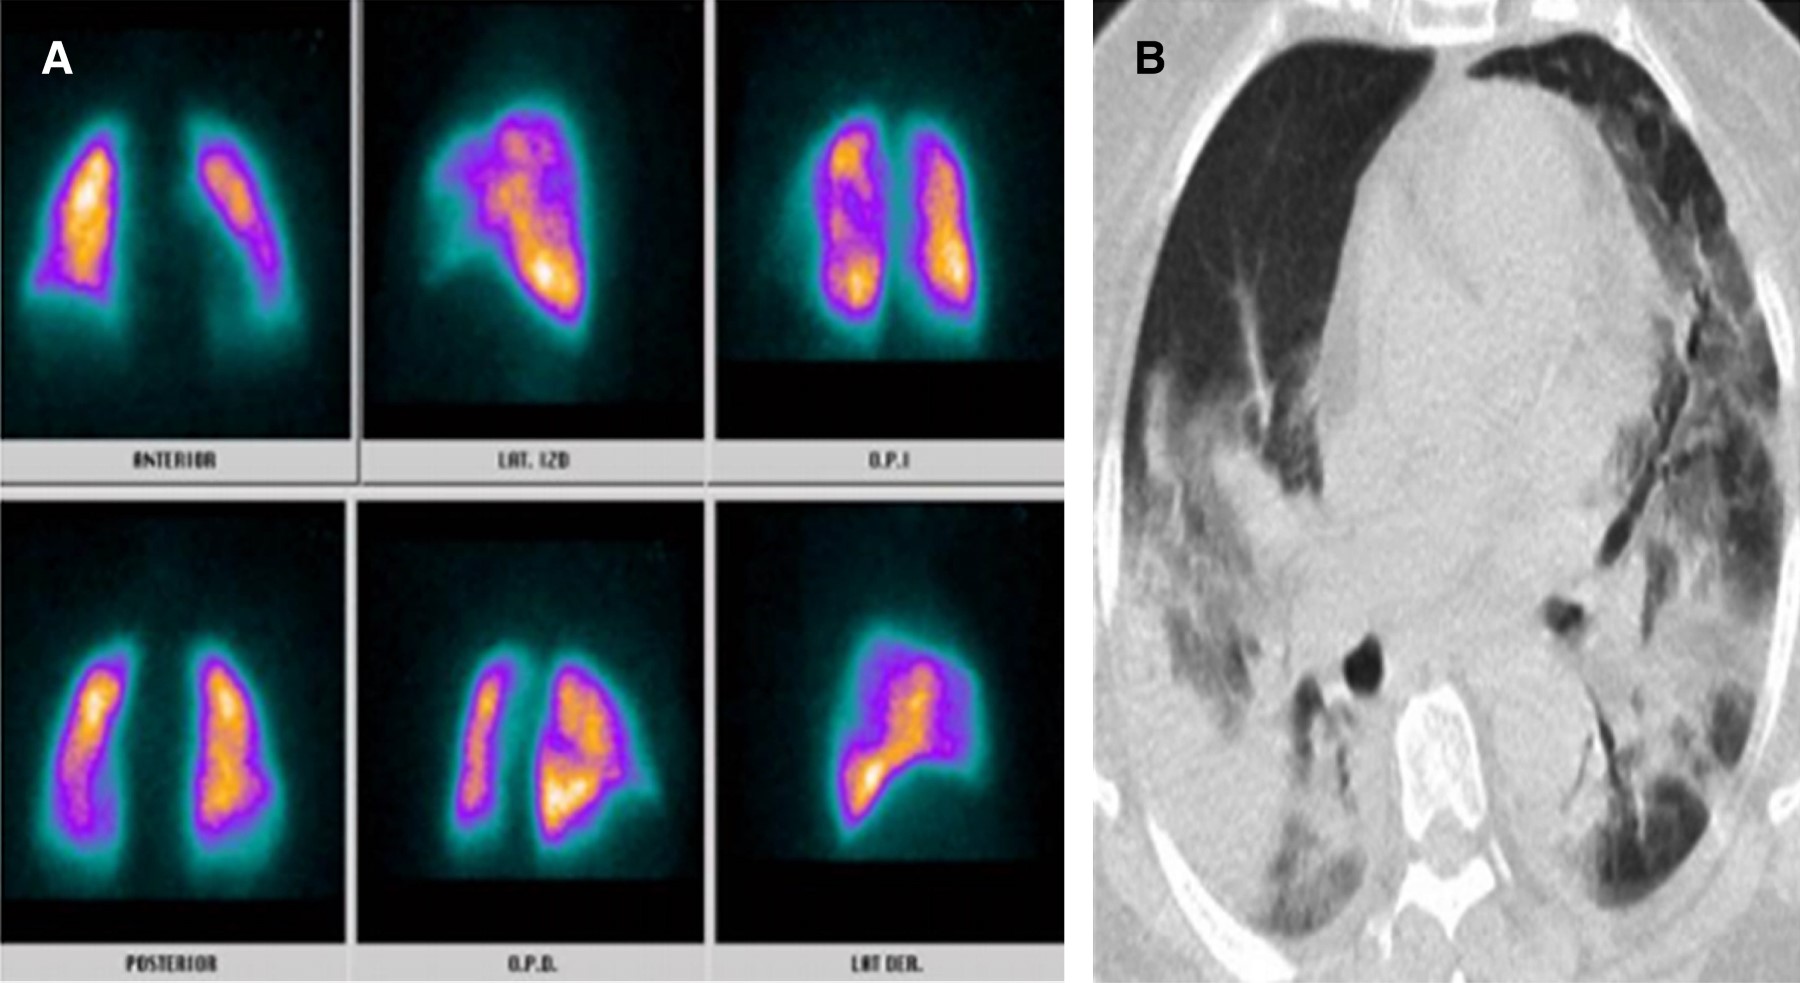

La infección por nuevo coronavirus es una entidad clínica altamente letal que trae consigo serias disfunciones celulares en primera línea de defensa, lo cual genera potentes mecanismos de hipercoagulabilidad mediados por reclutamiento de células inflamatorias.1 Uno de ellos direccionado por la disfunción del polimorfonuclear a partir del receptor 2 de enzima convertidora de angiotensina generado por la interacción de la fenilalanina ubicada en la porción 486 de la proteína de espiga del coronavirus, constituyéndose como el efecto más quimiotáctico existente, incluso superior al de la interleucina 8 (IL-8).2 A partir de esta situación, el reclutamiento del neutrófilo trae consigo la formación de una fina red inflamatoria inductora de integrinas denominadas NET (Neutrophil Extracellular Traps), produciendo activación de la vía intrínseca de la coagulación a partir del factor XII de Hageman. Adicionalmente, la muerte programada de dichas células, mediante la inducción de apoptosis, ocasiona liberación de histonas y restos de ADN, lo que precipita la formación de trombina.3,4 Por otro lado, la infección por nuevo coronavirus altera la respuesta del huésped al inóculo mediante modificación de los micro-ARN linfocitarios, lo que ocasiona disfunción del fagosoma natural en estadios de inmunocompetencia exacerbada o inmunosupresión manifiesta que a la postre desencadena estrés oxidativo, liberando grupos de proteínas de elevada movilidad (High Mobility Protein Box 1 [HMGB1]) y generando inflamación, coagulación y apoptosis.5 Pero, sin duda alguna, la linfopenia inducida por el coronavirus tipo 2 se constituye como el determinante más letal de trombosis mediante activación de la vía extrínseca e intrínseca de la coagulación, de la mano de un influjo descomunal de trombina. Se han identificado tres mecanismos de muerte celular programada en el linfocito de pacientes con la enfermedad por coronavirus del 2019 (COVID-19); uno de ellos es por activación del factor de transcripción nuclear y factor nuclear kappa beta, otra es por la activación del mitógeno p37 de la proteincinasa y la más deletérea mediante autofagocitosis determinante de un potente estado protrombótico.6 Con base en el conocimiento de los escenarios disfuncionales hematológicos durante la infección por nuevo coronavirus, se hace perentoria la predicción de enfermedad pulmonar tromboembólica, existiendo la duda razonable entre la prevención y la terapia antitrombótica, motivo por el cual la presencia de marcadores de actividad de fibrinolítica debe ser validada en tiempo presente y real. Teniendo en cuenta la mejor sensibilidad y especificidad disponible, las diferentes técnicas de enzimas líticas de inmunoensayo, hemaglutinación y látex deben someterse a consideración durante la estratificación diagnóstica.7,8 Una vez discriminados los pacientes con SARS-CoV-2 con pretest clínico medio para enfermedad pulmonar tromboembólica con reporte de dímero D por técnica de látex positivo y cuyos resultados de angio-TAC descartaron tromboembolia pulmonar (TEP); se les documentó, desde el punto de vista imagenológico, los defectos segmentarios de distribución vascular con morfología triangular de base externa y vértice interno por medicina nuclear, los cuales se correlacionaron muy de cerca con hallazgos en escanografías simples de tórax con atelectasias, efusión pleural y condensaciones, así mismo la presencia de alta probabilidad para TEP se validó por criterios de PISAPED (Figura 1, 2, 3, 4, 5, 6 y 7).9

Figura 4